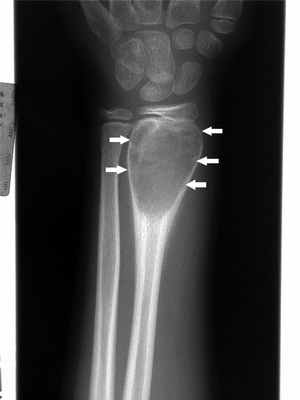

(Слева) Рентгенография в ПЗ проекции: типичный крупный костный островок. Равномерный участок склероза с краями в виде щетки, которые переходят в нормальную кость. Четкий склерозированный край отсутствует.

(Справа) МРТ, корональная проекция, режим Т1: сигнал низкой интенсивности от патологического очага у этого же пациента близкий к таковому от кортикальной кости. Край в виде щетки образует верхнюю границу патологического очага, которая переходит в нормальную кость, что является типичным признаком костного островка. (Слева) МРТ, сагиттальная проекция, режим Т2: у этого же пациента визуализируется патологический очаг, характеризующийся гомогенным сигналом низкой интенсивности, который идентичен сигналу от кортикальной кости. Интенсивность сигнала является типичным признаком, который не требует контрастного усиления.

(Справа) МРТ, сагиттальная проекция, режим Т2 с подавлением сигнала от жира: в той же зоне, что и на предыдущем изображении в режиме Т2 сигнал от костного островка имеет интенсивность минимально превышающую В таковую от костной ткани, окружающей костный островок в режиме насыщения жира. Этот признак типичен для костного островка и не должен расцениваться как проявление метастаза.

б) Визуализация:

• Рентгенография в большинстве случаев позволяет установить правильный диагноз:

о Гомогенный участок уплотнения, угасающего к периферии с переходом в нормальную трабекулярную структуру

о Края участка имеют вид щетки; могут быть звездчатыми

о Ассоциированный отек костного мозга или кортикальная деструкция отсутствуют

о Поражение может быть полиоссальным

• КТ позволяет более четко визуализировать периферические особенности очага:

о Уплотнение угасает к периферии с последующим переходом в нормальную трабекулярную структуру

• МРТ: сигнал низкой интенсивности во всех последовательностях:

о В режиме насыщения жира отмечается чуть более высокая интенсивность сигнала по сравнению с нормальной костью

о Не контрастируется

• Сцинтиграфия: может быть нормальной, но часто положительная:

о Зависит от размера патологического очага; несколько повышенное накопление наблюдается при очагах размером > 1 см

о Не позволяет достоверно дифференцировать костный островок и метастаз

• Наиболее часто поражаются таз, длинные трубчатые кости, ребра и позвоночник:

о Поражаться может любая кость

в) Диагностическая памятка:

• Диагностика вызывает затруднение только у лиц пожилого возраста, которые подвержены риску склерозирования метастазов:

о Полиоссальное поражение с несколько большей вероятностью, но не всегда, свидетельствует о метастазах

о При сцинтиграфии наблюдается повышенное накопление, как при эностозе, так и при склерозировании метастаза

о МРТ в режимах Т1 и Т2 может характеризоваться идентичными признаками; при метастатическом поражении обычно наблюдается контрастное усиление, как минимум на периферии

о В редких случаях для дифференциальной диагностики требуется биопсия

• Периферический край патологического очага нечеткий, переходит в нормальную кость, имеет пальцевидные ответвления